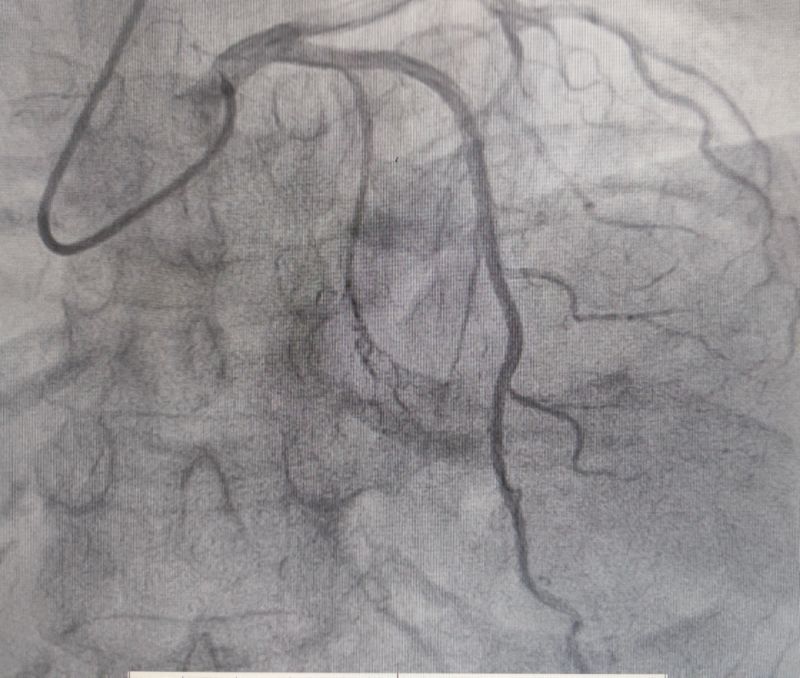

左室造影(左心室收縮期)

72歲的王女士(化名),早在7年前就被心臟彩超確診為室間隔肥厚并流出道梗阻。近期,她因“反復胸悶、氣短20余年,加重伴惡心、嘔吐1周”入住消化內科。入院復查心臟彩超結果顯示:EF值為62%,FS值為34%;室間隔中上段厚度達到18.5/17.7毫米,左室流出道最大血流速度高達547cm/s,PG值為119mmHg,明確診斷為梗阻型肥厚型心肌病。同時,腦鈉肽檢測值為3050.6ng/l。綜合評估后,王女士轉入心血管內科九病區接受進一步治療。

術前